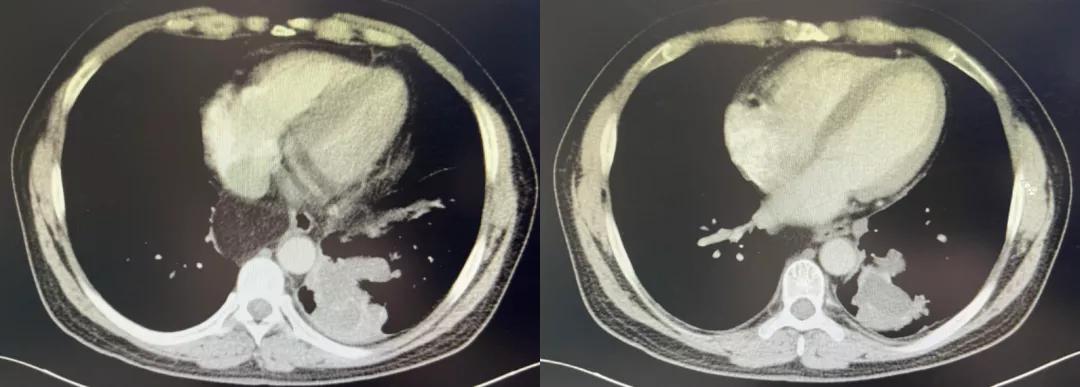

2019年12月5日胸部CT:1、左肺下叶后基底段见不规则团片影,较大层面约5.8×4.6cm,其内见少许点状钙化灶,周围见斑片、条索影,邻近胸膜增厚、黏连。2、右肺中叶、左肺下叶、左侧斜裂小结节,较大者约0.4cm,多系炎性。3、双肺少许慢性炎症。4、心脏未见增大,肺动脉干稍增粗。5、左肺门淋巴结稍大。6、食管裂孔疝。(图1)。

图1:胸部CT 2019年12月5日

2020年3月17日胸部CT:1、左肺下叶后基底段见不规则团片影,较大层面约6.2×5.1cm,其内见少许点状钙化灶,周围见斑片、条索影,邻近胸膜增厚、黏连。2、右肺中叶、左肺下叶、左侧斜裂小结节,较大者约0.4cm,多系炎性。3、双肺少许慢性炎症。4、心脏未见增大,肺动脉干稍增粗。5、左肺门淋巴结稍大。6、食管裂孔疝(图3)。

图3:胸部CT 2020年3月17日